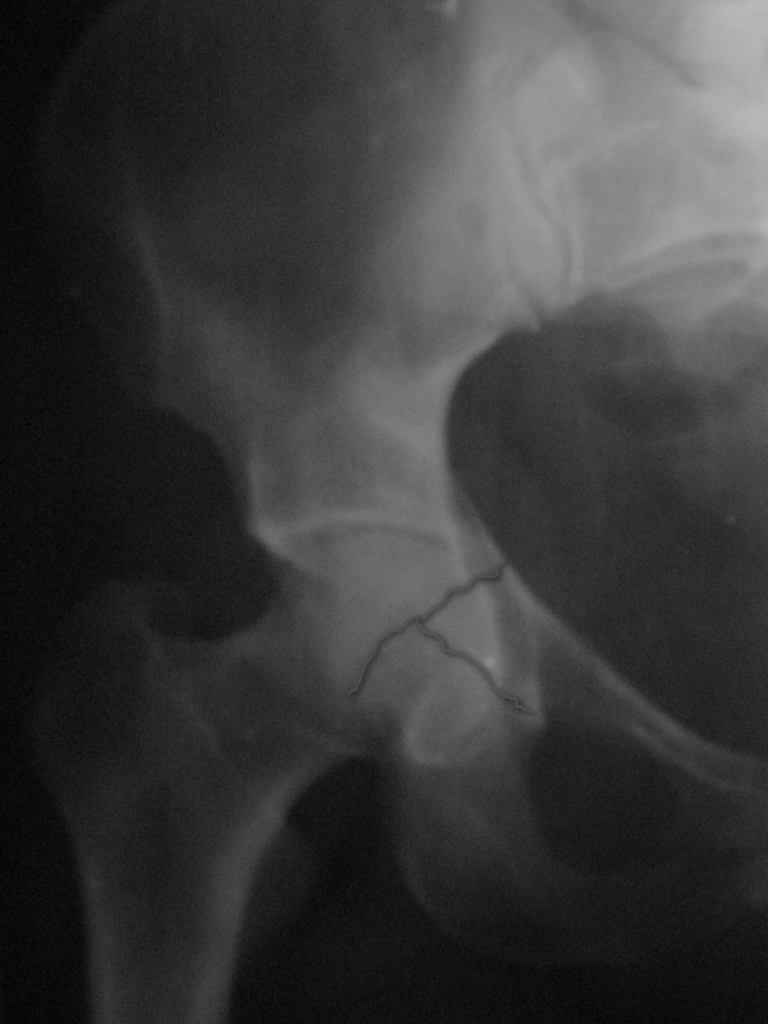

Женщина,58 лет, после ДТП 6 суток. Первично повреждение расценено как переломы ветвей лонной кости. После подтверждения повреждения вертлужной впадины,как чаще всего случается, вопрос встал о тактике. БОльшинство за консерватиное лечение.К сожалению кт у нас "во время" сломался. Прилагаю стандартные снимки вертлужки. У меня следующие вопросы к коллегам:1. Правильно ли рассценивать это повреждение как Т-образный перелом вертлужнй впадины?2. Можно ли добиться анатомической репозиции поверхности вертлужной впадины скелетным вытяжением в данном случае, если нет, что будет этому препятствовать?3. Если смещение останется таким как сейчас, через какое время появится необходимость эндопротезирования (по вашему опыту)?Спасибо.

имеется передний подвывих, головка нагружаемой зоной будет "тереться" о край фрагмента, связанного с осевым скелетом.

вероятность быстрого прогрессирования коксартроза велика, хотя вряд ли кто-то укажет конкретные сроки. 1 год - 1,5 ?

Уважаемый Коваленко А.Н., снимки плохого качества и нет уверенности, что задняя колонна сломана (смещена). Если кт нет - везите больную в рентгенкабинет (палатником качественные снимки снимки не получатся) и сделайте обзорный снимок таза, Judet и может быть inlet, хуже вы ей не сделаете.

Вытяжение не поможет в любом случае, т.к. потянуть за одну переднюю колонну не получится. Есть вариант закрытого лечения, но для этого нужно наоборот сдавить крылья (скажем аппаратом), если больше переломов переднего полукольца нет, то передний подвывих уменьшится.